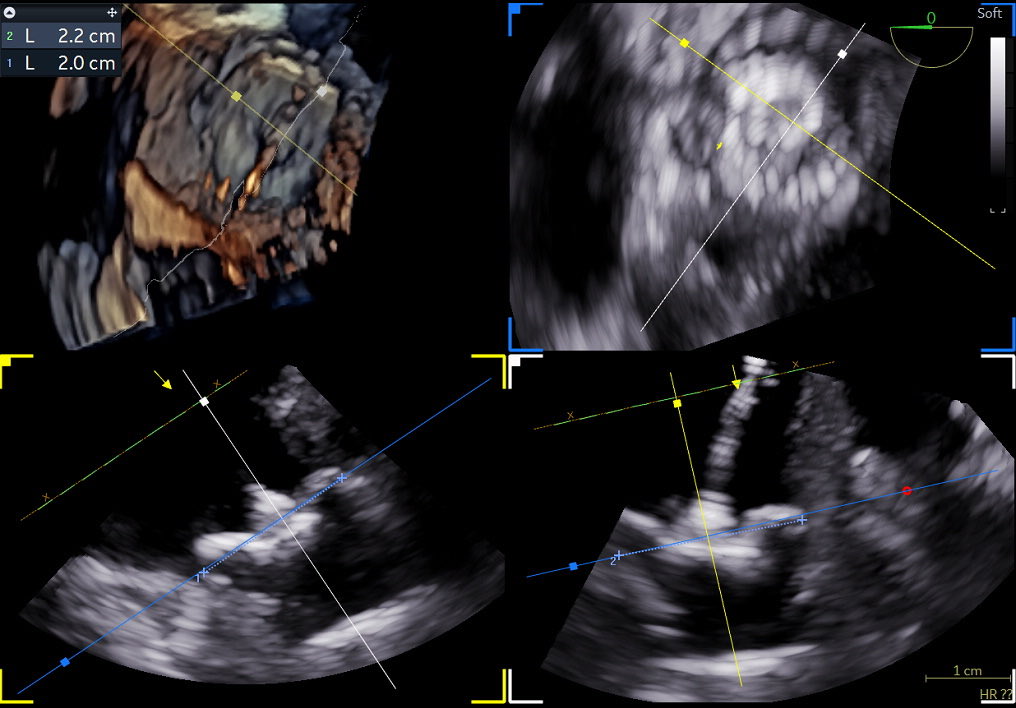

Nuvision Nav catheter @JNJMedTech, first case in New Jersey @RutgersNJMS, @UnivHospNewark in a concomitamment PFA and WATCHMAN procedure, great images and streamline.

English